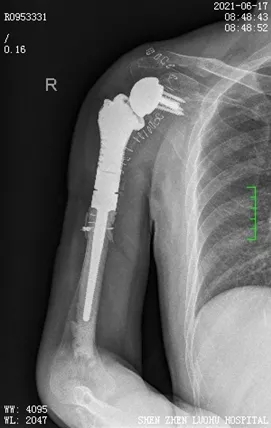

由于宋先生右侧肩关节周围肌肉萎缩严重,软组织条件差,经讨论决定,为其量身定制人工肩关节假体。经过充分的术前准备,杜教授为患者进行了右侧人工全肩关节置换、重建、植骨+左侧髂骨取骨术,手术过程顺利,术后恢复良好。

术后,宋先生看到自己的右侧肩关节外观变得饱满,感觉不可思议,脸上不自觉就露出开心的笑容。